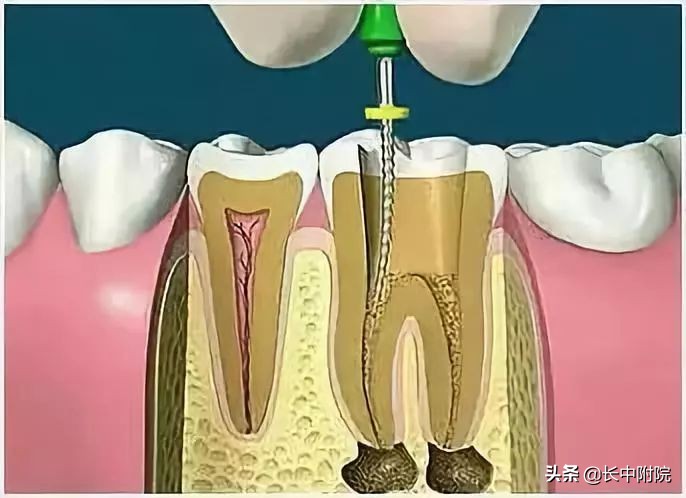

4.根管预备

根管清理成形的目的是去净根管壁上的感染物,通过根管器械的切削作用去除感染的牙本质并清理根管壁细菌以利于根管充填。